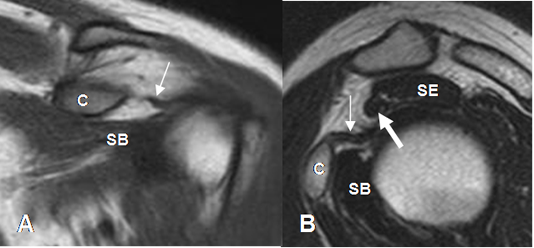

La artroresonancia (ArtroRM) es la mejor técnica para evaluar los ligamentos y el labrum glenoideo. (Fig 23 a 26). La aplicación de la mezcla intra-articular del contraste, puede hacerse mediante guía fluoroscópica o ecográfica. (13). La ecografía se considera la técnica mas fácil, rápida y menos dolorosa. (13). (Fig 22).

Fig 22. Técnica de ArtroRM por ecografía.

A: RM axial en FFE y B: Ecografía vista axial. Abordaje anterior, con trayecto de la aguja en el espacio coracohumeral. Al atravesar el subescapular (Flechas gruesas), se inyecta el contraste.

C: Ecografía axial. Aguja (Flecha delgada) cruzando el músculo subescapular. (Flecha gruesa).